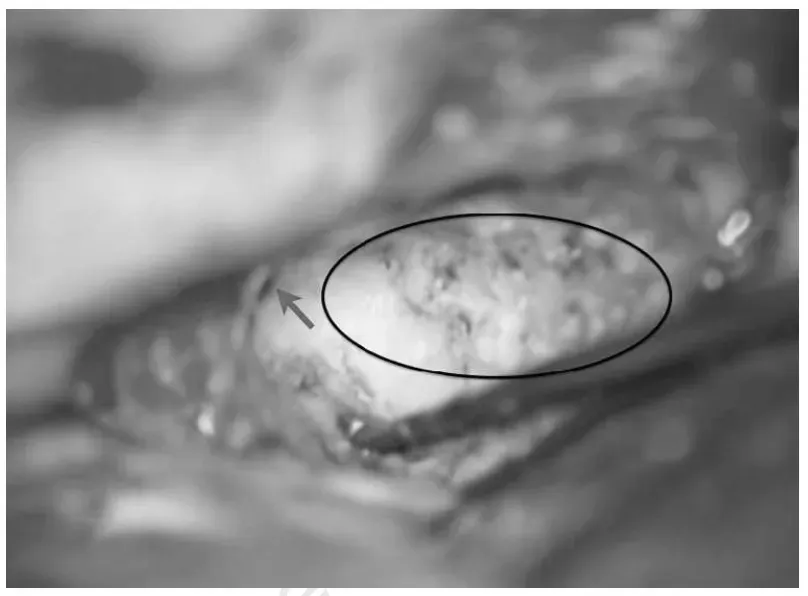

椭圆形区域显示前岩骨切除术后被移除的岩骨部分,箭头指示钻磨后部结束边缘